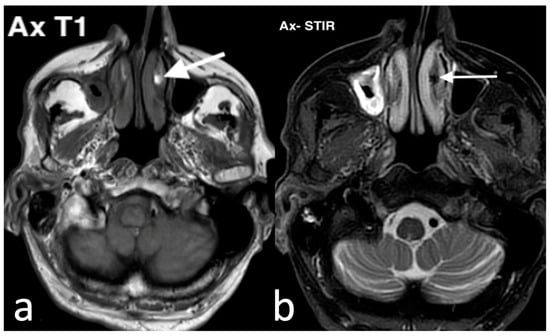

3.1.3. Inverted Mesiodens